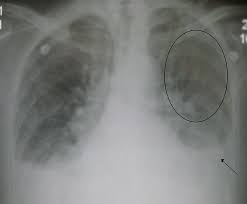

Rontgen Thorax Lunge Grunde Ablauf Bilder Praktischarzt